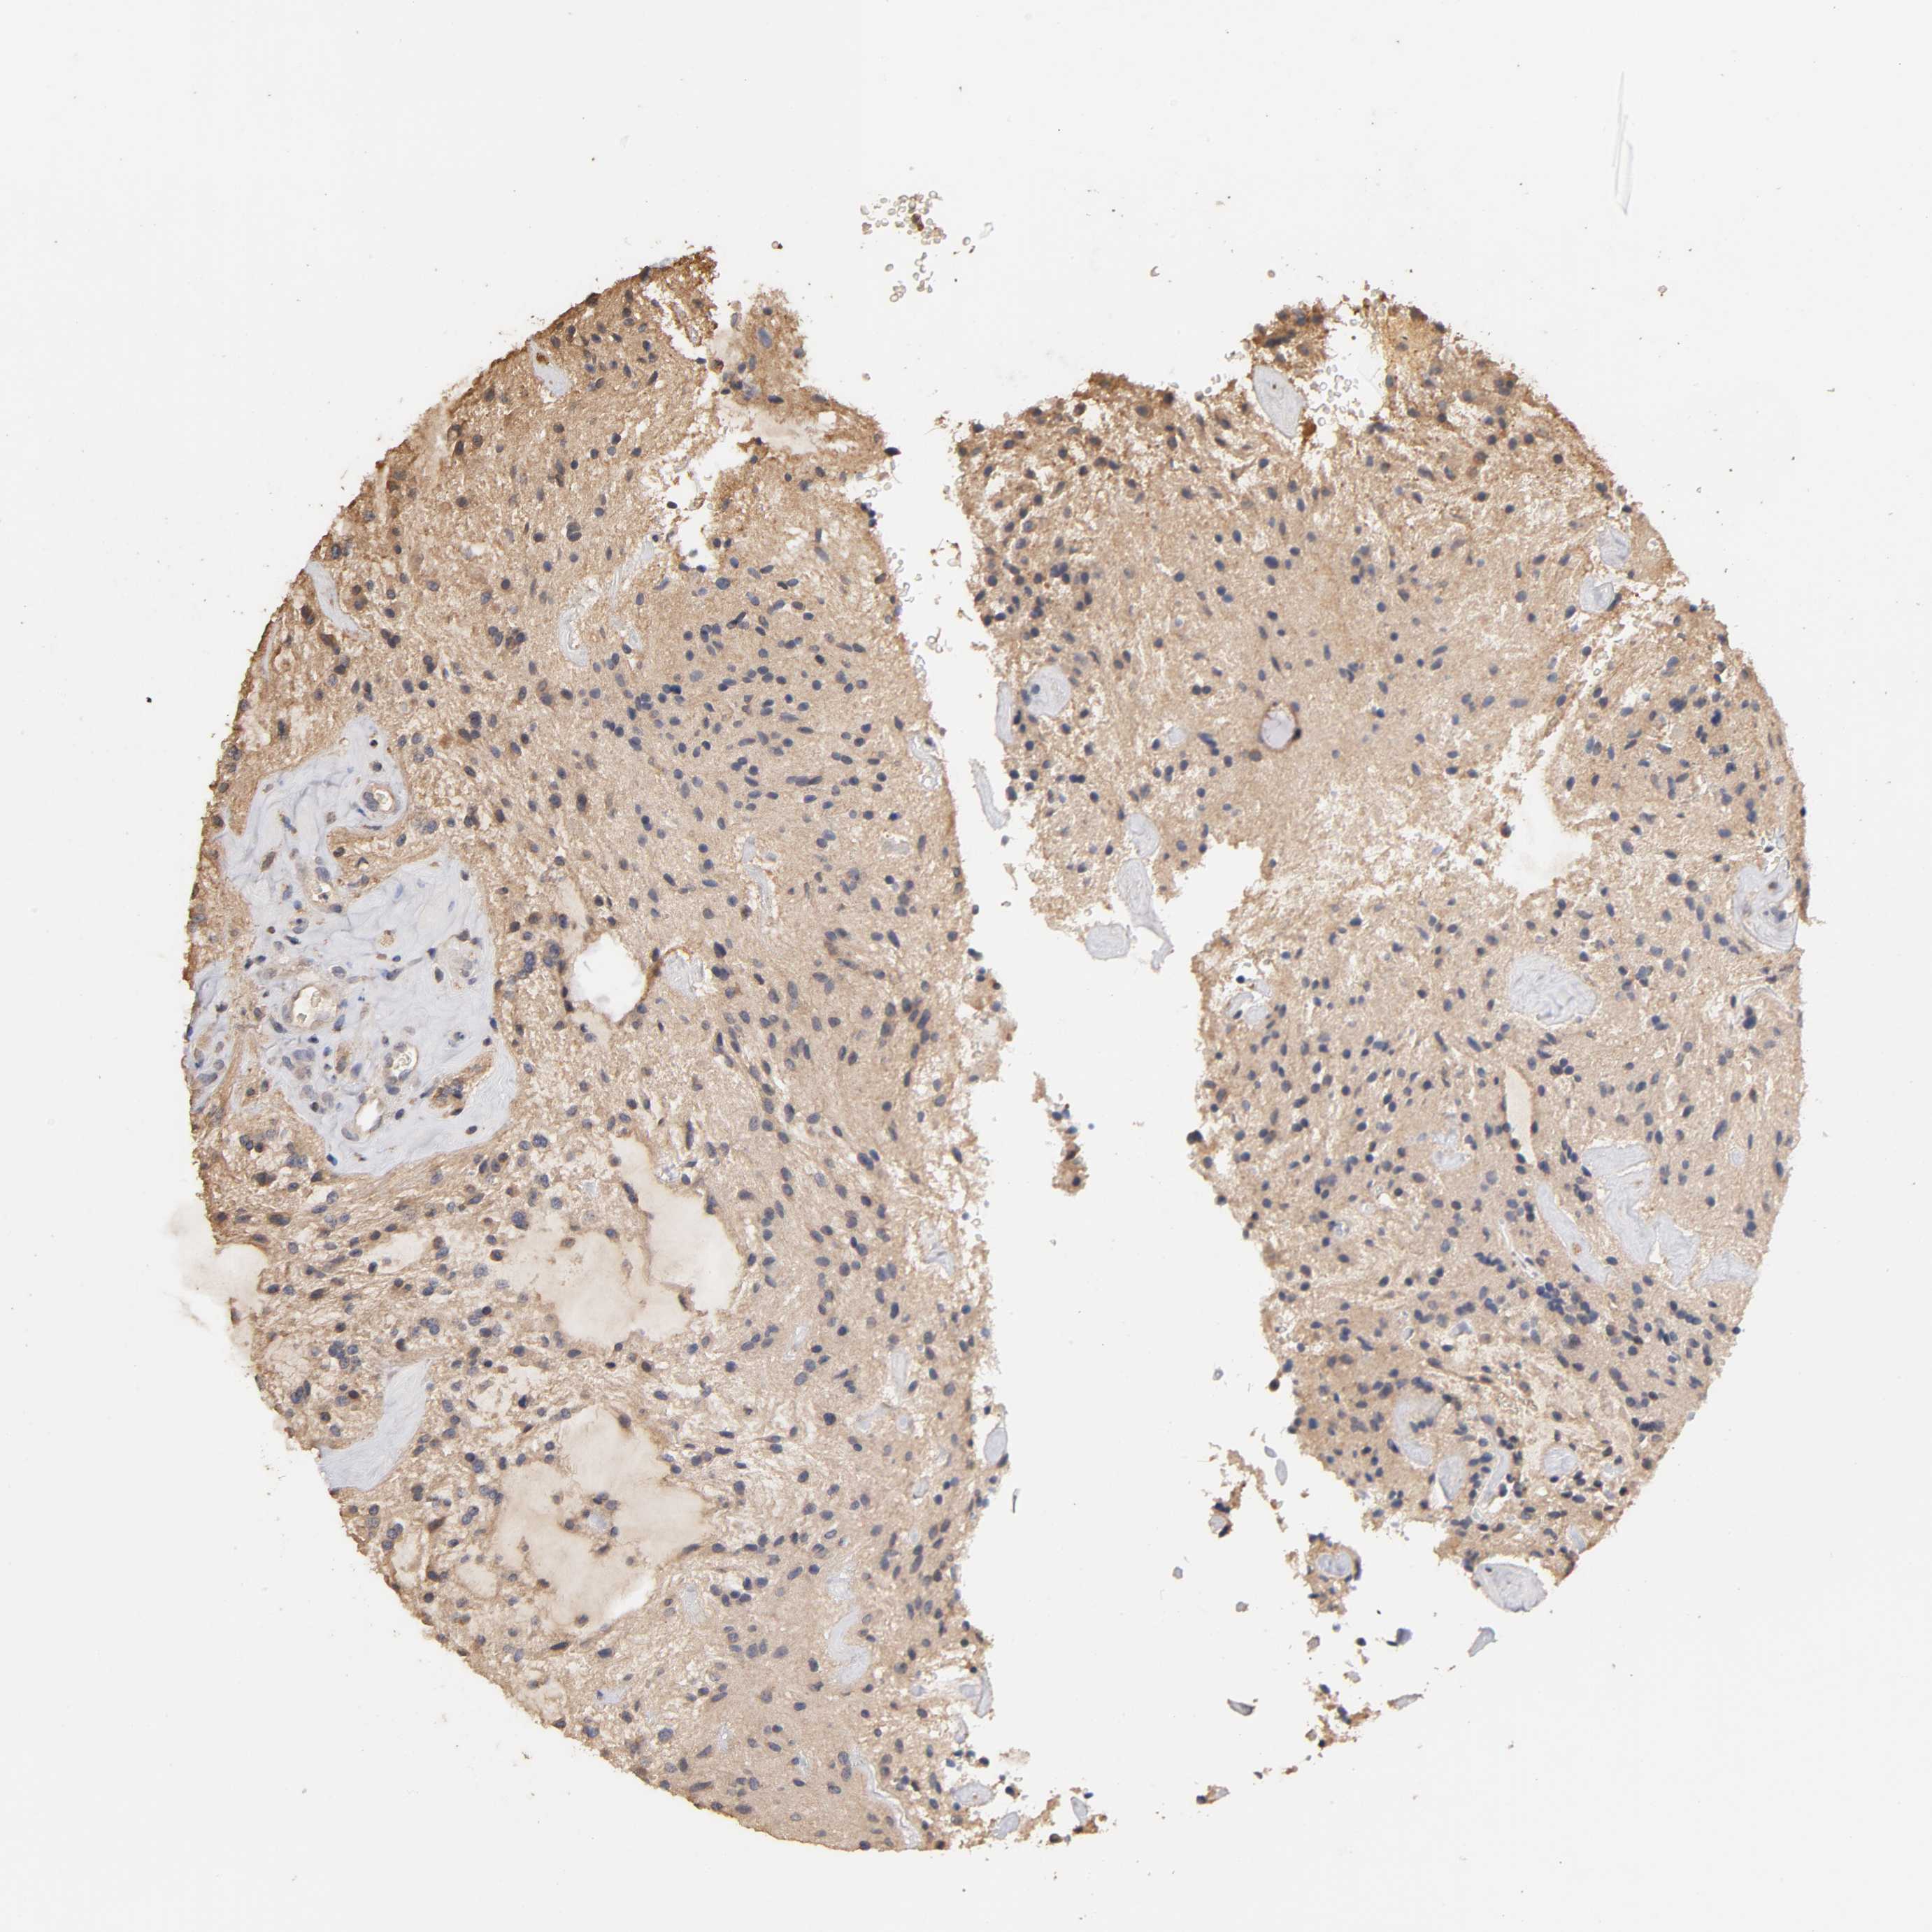

GLIOMA - Protein expressioni

A mouse-over function shows sample information and annotation data. Click on an image to view it in a full screen mode. Samples can be filtered based on level of antibody staining by selecting one or several of the following categories: high, medium, low and not detected. The assay and annotation is described here.

Note that samples used for immunohistochemistry by the Human Protein Atlas do not correspond to samples in the TCGA dataset.

Antibody stainingi

Antibody staining in the annotated cell types in the current human tissue is reported as not detected, low, medium, or high, based on conventional immunohistochemistry profiling in selected tissues. This score is based on the combination of the staining intensity and fraction of stained cells.

Each image is clickable and will lead to virtual microscopy that enables deeper exploration of all samples and also displays staining intensity scores, fraction scores and subcellular localization as well as patient and tissue information for each sample.

Antibody HPA003903

Antibody HPA072756

Antibody CAB026000

Staining

High

Medium

Low

Not detected

Intensity

Strong

Moderate

Weak

Negative

Quantity

>75%

75%-25%

<25%

None

Location

Nuclear

Cytoplasmic/membranous

Cytoplasmic/membranous,nuclear

Glioma, malignant, High grade

Glioma, malignant, NOS

Glioma, malignant, Low grade